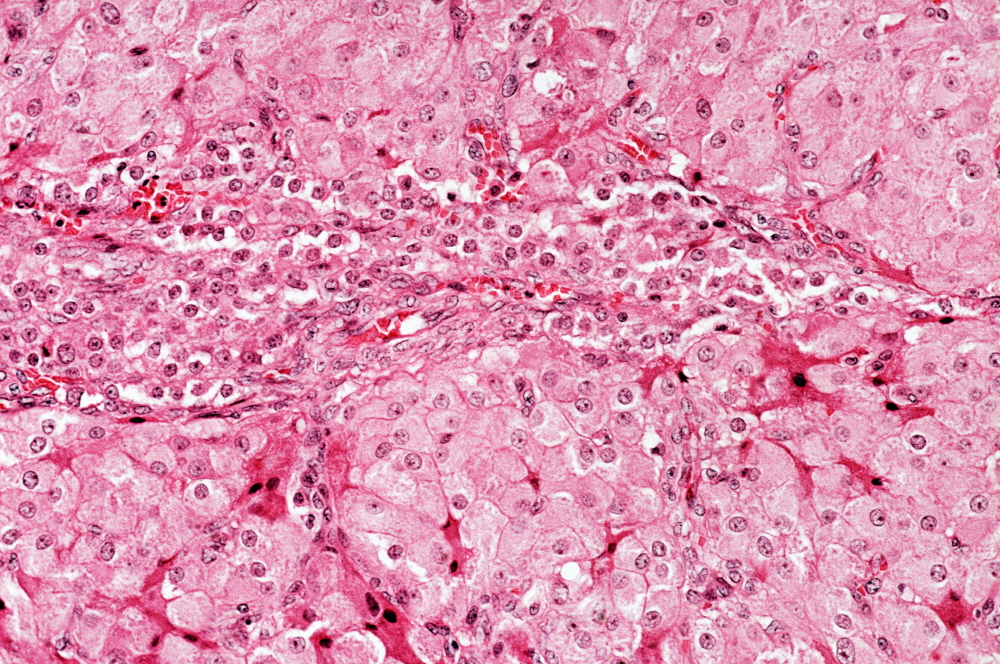

난소암

난소암은 여성의 난소에서 발생하는 암으로, 초기에 명확한 증상이 나타나지 않아 조기 발견이 어려운 경우가 많습니다. 하지만, 몇 가지 초기 증상을 인지하고 있다면 난소암을 조기에 발견할 가능성이 높아집니다.